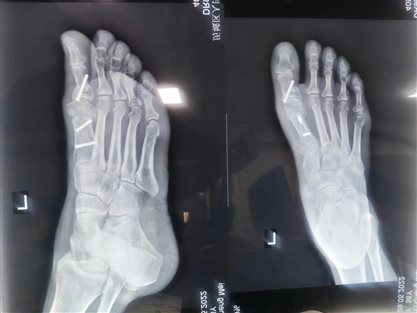

以下是我院外一科拇外翻患者手术前后对比:

术前

术后